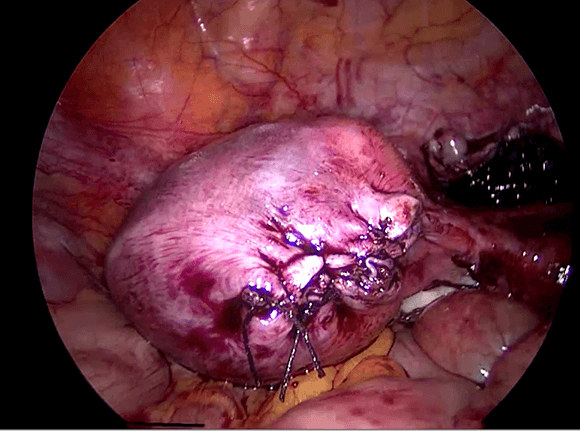

Saat kehamilan ektopik berada di daerah kornu rahim ( Gambar 7.4 ), maka kehamilan biasanya didiagnosis masih lama lagi. Kehamilan kornu jauh lebih sulit untuk dieksisi secara laparoskopi karena ukuranya lebih besar dan dapat berdarah dengan menyebar luas. Teknik ini melibatakan suntikan vasopressin disekitar kornu kehamilan ektopik dan penempatan jahitan purse string di sekitarnya. Kemudian sayatan dibuat untuk enukleasi kehamilan ektopik. kerusakan kemudian dijahit. Pada kehamilan kornu yang besar, bagian dari rahim harus diangkat bersama-sama dengan tuba. Pada kasus- kasus yang sulit, laparotomi mungkin diperlukan.

Reseksi laparoskopi kornu kehamilan ektopik

Pada tahun 2009 nyonya UDS datang mengunjungi saya , dia telah menikah 3 tahun dan dia tidak bisa hamil. Histerosalpingogram yang dilakukan di rumah sakit yang lain menunjukkan kedua tubanya tersumbat / terblokir. Dia menjalani laparoskopi , dan laparoskopi menunjukkan ukuran rahim yang normal. Kedua tuba nya normal dan dipatenkan setelah insulfasi tuba dilakukan dibawah tekanan. Dia hamil secara spontan 2 bulan setelah menjalani laparoskopi namun sayangnya kehamilan berakhir dengan aborsi yang terlewatkan. Dia telah menjalani evakuasi hasil konseptus. Pasca operasi , keadaan dia baik-baik saja akan tetapi tidak dapat hamil. Dia telah diberikan beberapa siklus klomifen sitrat namun tanpa membuahkan hasil. Pada tahun 2011, dia menjalani siklus inseminasi intrauterin setelah diberikan suntikan hormon perangsang folikel ( FSH ). Setelah prosedur dilakukan , dia hamil akan tetapi sayangnya kehamilan itu adalah kehamilan ektopik. Dia menjalani reseksi laparoskopi kornu kanan kehamilan ektopik di tahun 2011 ( Gambar 26.7 – 26.11 ) ( simak video 26.3 ). Pasca operasi di tahun 2013 dia menjalani histerosalpingografi dan menunjukkan bahwa tuba kiri tidak paten. Dia dapat hamil setelah menjalani IVF.

Kornu kehamilan ektopik tidaklah umum. Biasanya didiagnosisnya terlambat karena pasien dengan kondisi seperti ini tidak memliki banyak gejala-gejala. Pecahnya kehamilan ektopik pada kornu dapat menyebabkan pendarahan yang berlebihan. Pada pasien ini diagnosis dilakukan lebih awal karena dia menjalani IUI dan berada dalam pengawasan secara teratur. Eksisi telah dilakukan dengan berhasil secara laparoskopi.